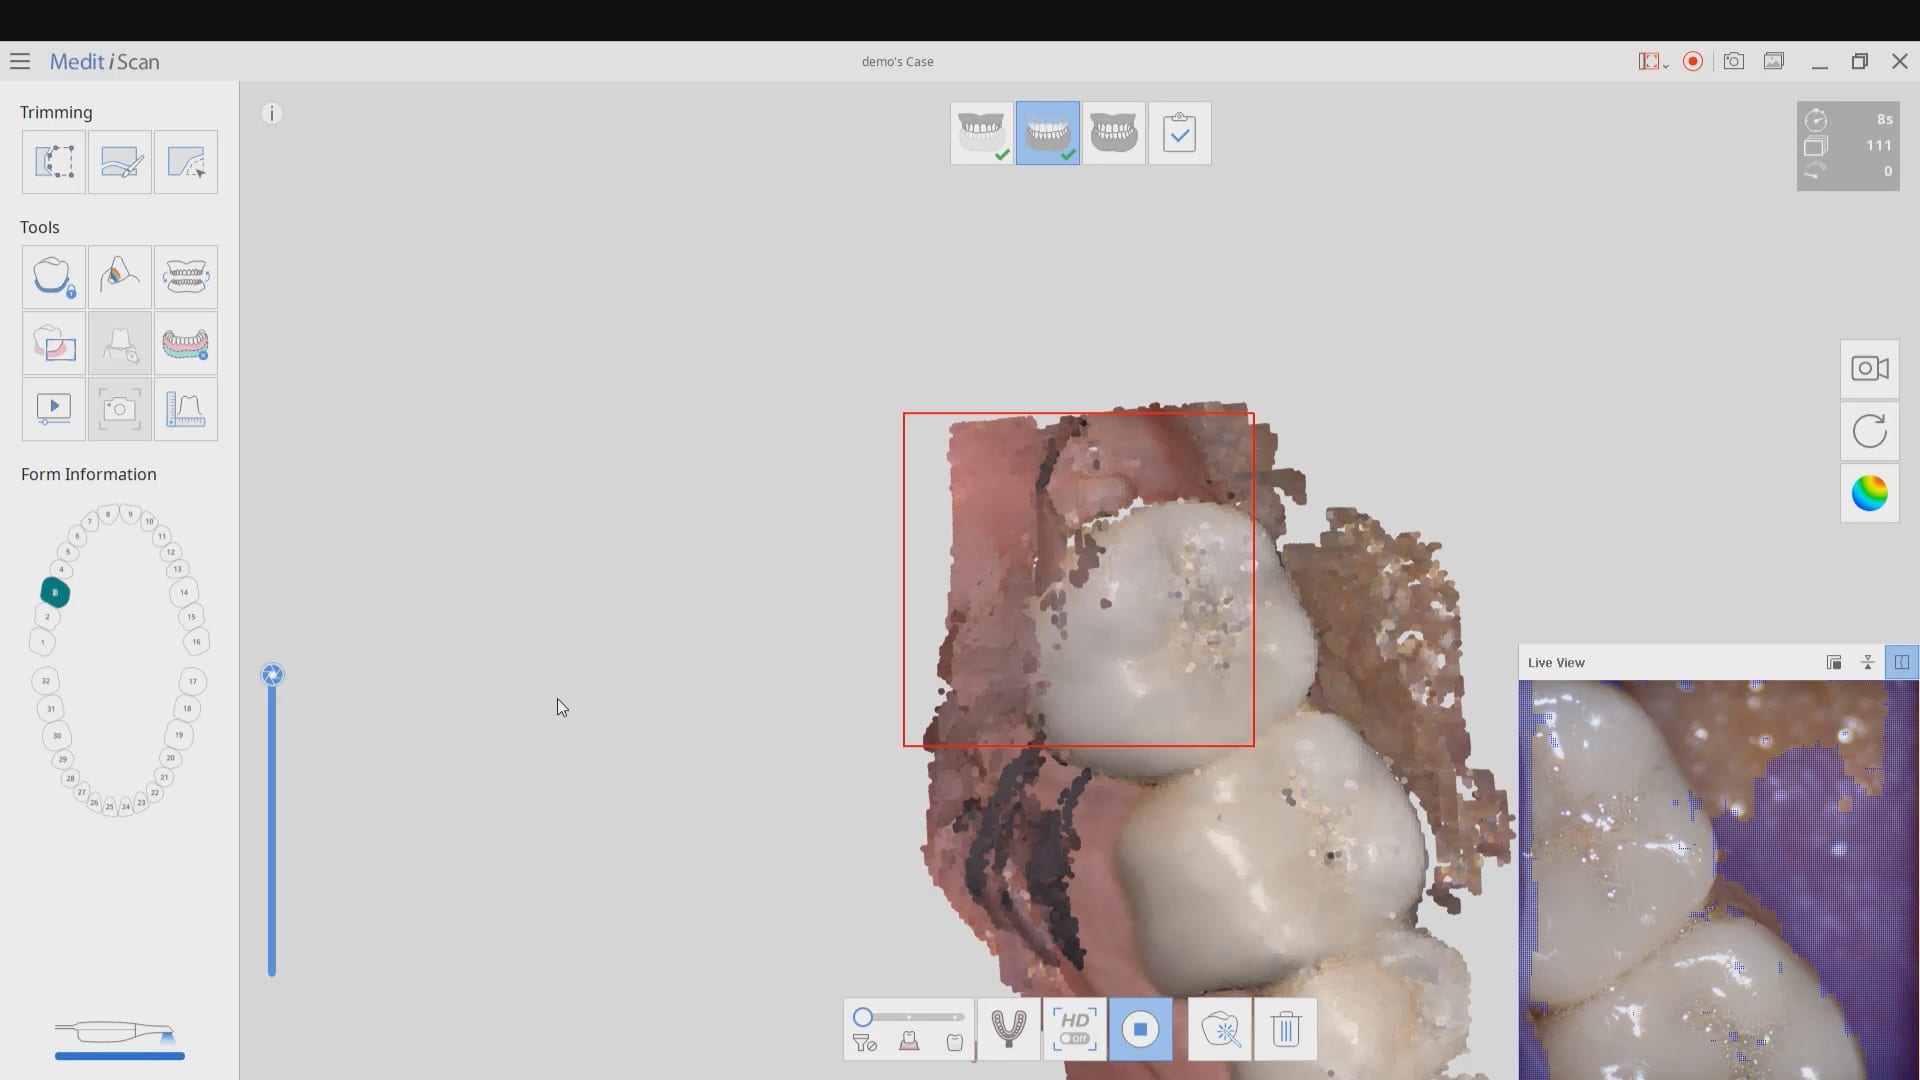

Where not to start with imaging with an intra-oral scanner

March 9, 2020Most manufacturers recommend that you start your imaging at the second molar area, which is the least practical area to start with. The tongue and the lip and saliva are […]